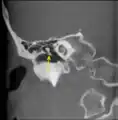

Chain of ossicles and their ligaments, seen from the front in a vertical, transverse section of the tympanum. CT image of malleus

CT image of malleus Auditory ossicles. Tympanic cavity. Deep dissection.